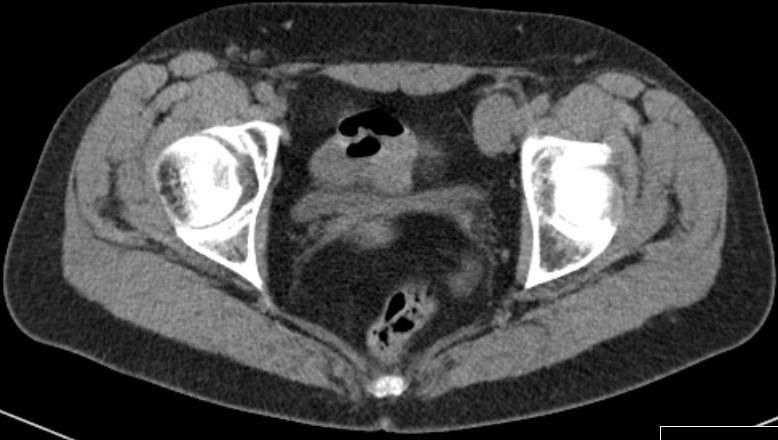

iliaca externa und inguinal |

59-jährige Frau mit einem Knoten in der linken Leiste.![]() |

![]() |

![]() | |